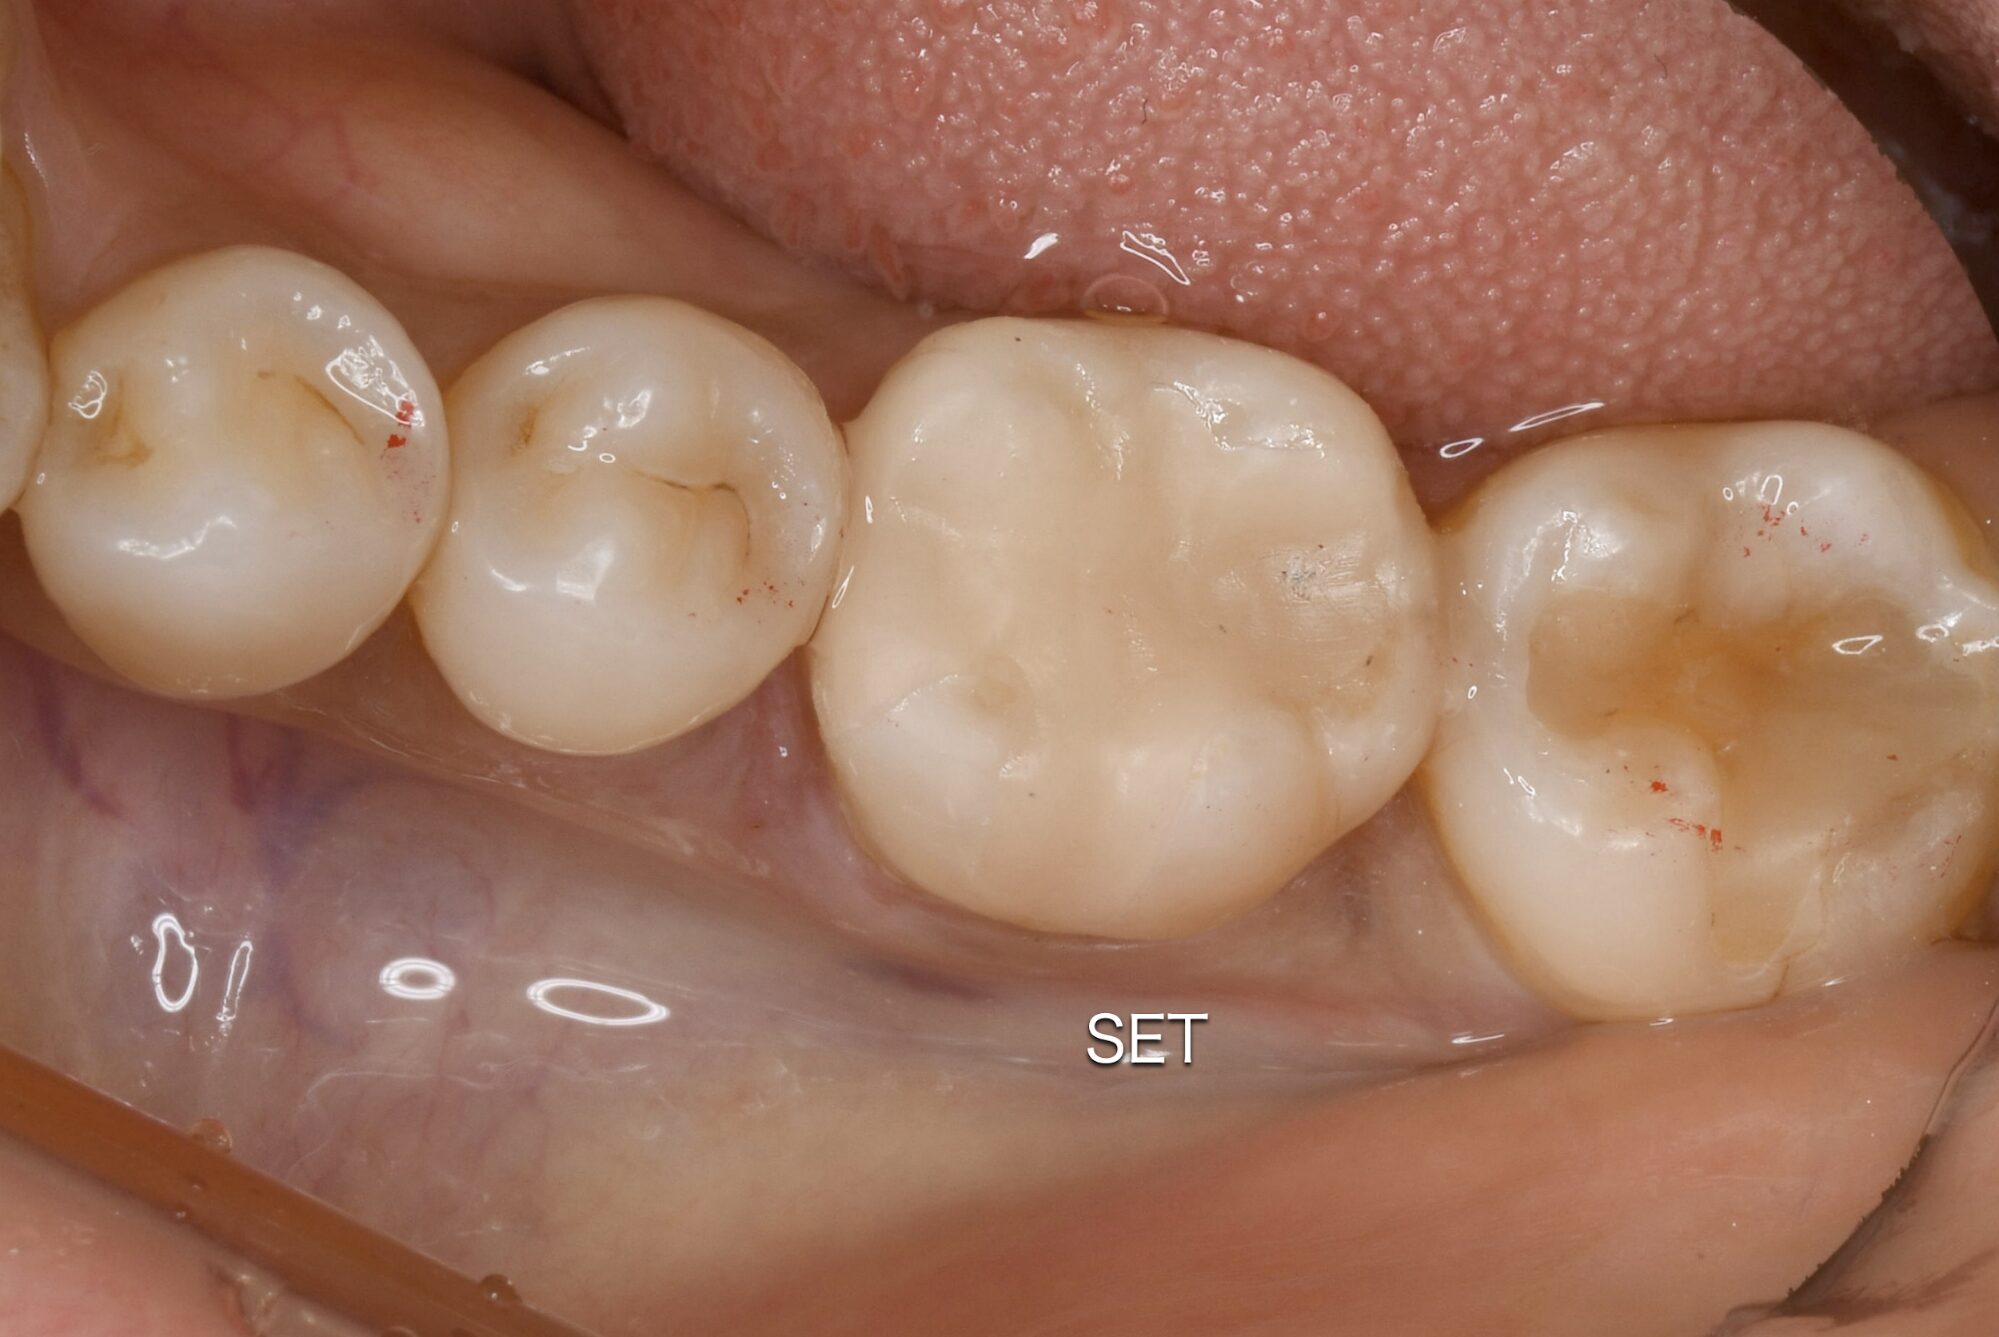

削り出されたセラミックが、お口の中でピッタリと適合するかをチェックします。

セラミック専用の強力な接着剤(レジンセメント)を使用して、歯に一体化させます。

この「接着」の工程を丁寧に行うことが、将来的な二次むし歯を防ぐ鍵となります。最後に、全体の噛み合わせを微調整し、表面をツルツルに研磨して終了です。

治療開始から約60分後、患者さんの下の奥歯には、どこを治療したかわからないほど自然で白い歯が入りました。

治療回数: 1回

所要時間: 60分

費用: 66,000円(税込)